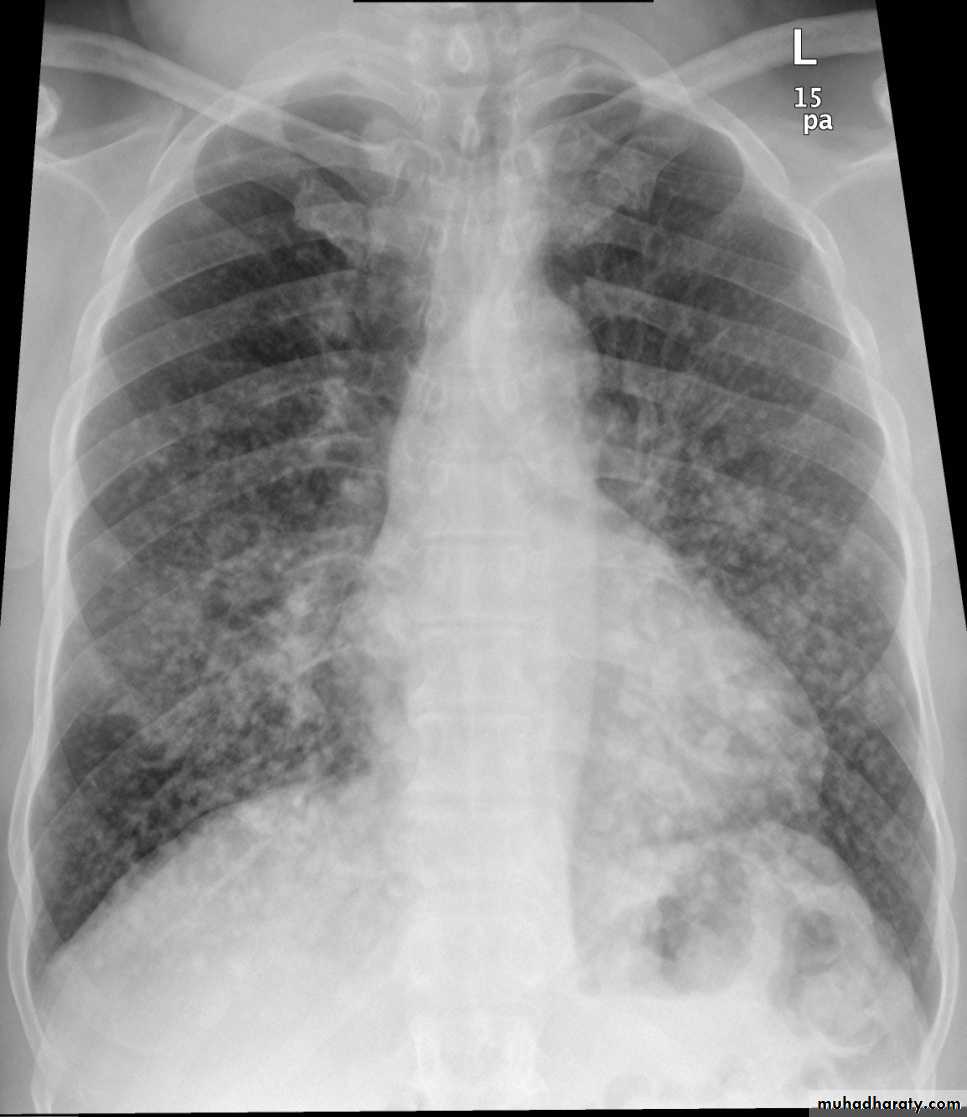

2.lymphangitis carcinomatosis , is the term given to tumor spread through the lymphatics of the lung , and is most commonly seen secondary to adenocarcinoma Unfortunately up to a quarter of patients with subsequently established lymphangitic carcinomatosis have normal chest x-rays . When abnormal the most common finding is of a reticulonodular pattern, with thickening of the interlobular septae which may resemble Kerley B lines + /- pleural effusion .